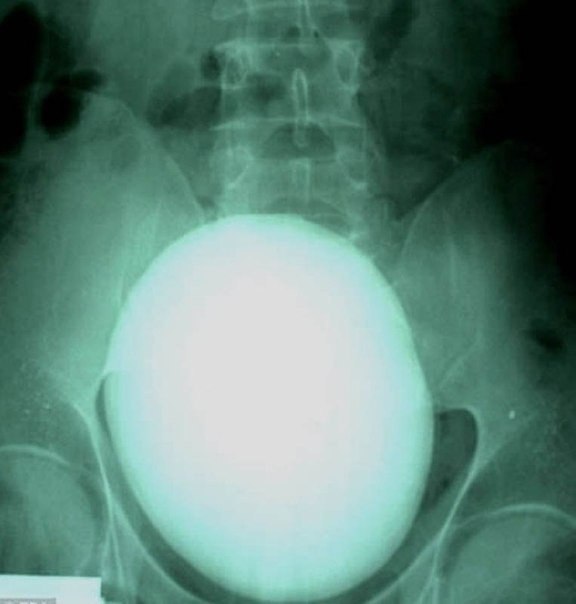

7> Se le extrajo un cálculo renal de 15 centímetros de largo y que pesaba 1,1 kilogramos a un paciente de Hungría